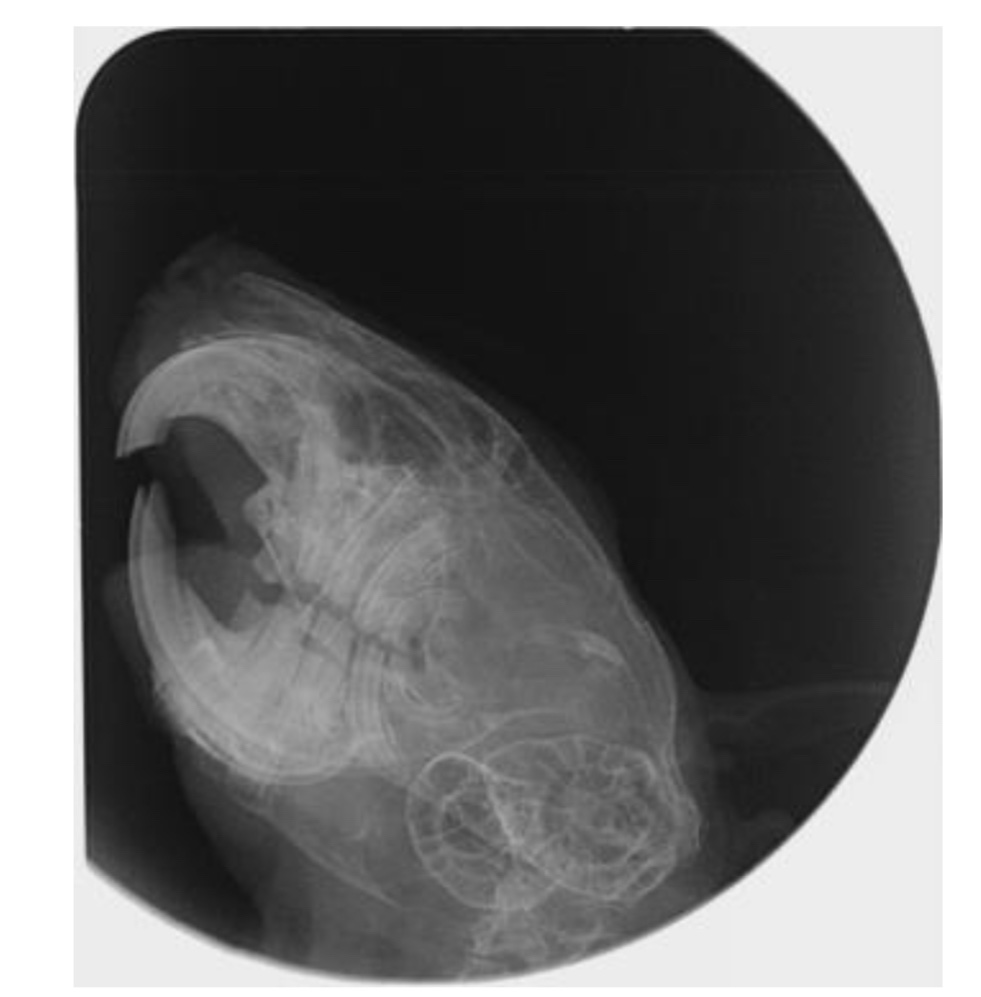

Hallo, Santiago wurde inzwischen unter einer Gasnarkose geröntgt- und hat es überlebt. *nicken* Die Tierärztin meinte, dass er ein Odontom (wuchernde Zahnwurzel?) hat, aber dies noch nicht so schlimm sei, dass man die OP riskieren würde. (Da müsste man von außen an den Kiefer ran)

Ich hänge mal die Röntgenbilder an- leider erkenne ich dort garnichts. Kann einer von euch etwas dazu sagen, wie schlimm es ist?

868C4BBF-A853-4301-AD97-6AB0E1983870.jpeg

868C4BBF-A853-4301-AD97-6AB0E1983870.jpeg (53.59 KiB) 2172 mal betrachtet